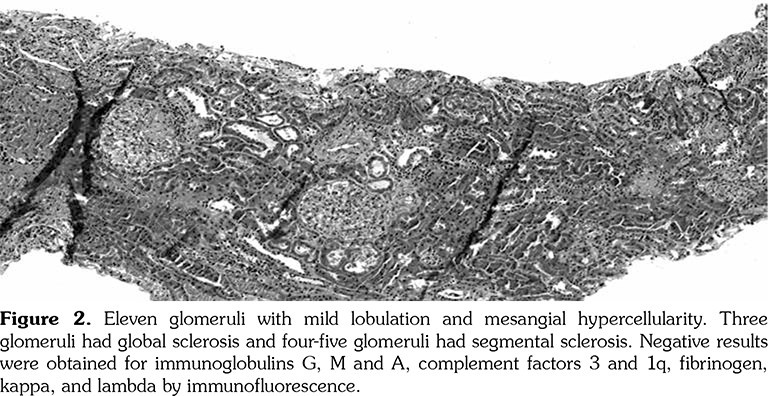

A 14-year-old female patient referred to our clinic with headache and dizziness for two weeks and loss of consciousness for about 10 minutes. On admission, the blood pressure was 90/60 mmHg and all peripheral pulses were palpable. Her body weight was above 97th percentile for her age and body mass index was 33. The fundus examination and other organ systems were essentially normal. Laboratory studies revealed erythrocyte sedimentation rate (ESR) as 108 mm/hour and C-reactive protein (CRP) as 7.5 mg/dL (0-0.8), while other measurements were normal. Urinalysis revealed microscopic hematuria and proteinuria of 31.9 mg/m2/hour in 24-hour urine collection. The cerebrospinal fluid examination showed no abnormalities. Cranial magnetic resonance imaging (MRI) showed multiple millimetric hyperintense deep white matter lesions on T2-weighted imaging (Figure 1). Intracranial and extracranial arteries were normal in magnetic resonance angiography (MRA). Renal biopsy findings were interpreted as FSGS (Figure 2). Patient was considered as cerebral vasculitis and incidental FSGS. Pulse methylprednisolone therapy for three consecutive days was initiated and continued with oral prednisolone. At four years of follow-up, proteinuria decreased to 5-15 mg/m2/hour, and ESR and CRP were normal. Repeated brain MRI and MRA examinations showed no new lesions. Four years later, at the age of 18, on a routine examination, both radial artery pulses were absent and the blood pressure could not be measured. Significant bruit was heard on the left carotid artery. Laboratory studies revealed ESR as 43 mm/hour and CRP as 2.46 mg/dL. Aortic MRA revealed diffuse wall thickening and contrast enhancement in the arcus aorta and its many main branches (Figure 3). Takayasu arteritis diagnosis was established according to the European League Against Rheumatism/ Paediatric Rheumatology International Trials Organisation/Paediatric Rheumatology European Society criteria.[2] Methotrexate was begun, and daily prednisolone was continued. Four months after the diagnosis of TA, left-sided hemiparesis developed. Brain MRI demonstrated a wide cerebral infarct at the right anterior vascular territory (Figure 4). Brain and neck computed tomography angiography showed total occlusion of the right internal carotid artery. Vascular involvement of the right common carotid artery was progressed to preocclusive stenosis. Diameters of the right anterior and middle cerebral arteries were thin and fed by the posterior and anterior communicating arteries (Figure 5). Tocilizumab treatment was started at 8 mg/kg every four weeks. At follow- up with 2.5 years of tocilizumab treatment, the patient's clinical condition improved slightly, and no new symptoms developed. A written informed consent was obtained from the patient.